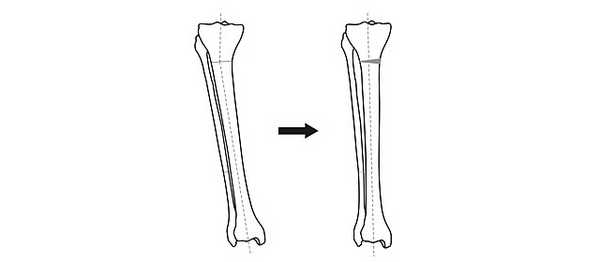

Схема исправления оси большеберцовой кости

Для выполнения остеотомии вовсе не обязательно делать большой разрез кожи. Достаточно небольшого (5 мм) прокола и наложения одного шва. При эстетически благоприятном распределении мягких тканей на голени отличного результата можно добиться, не пересекая кость полностью, а лишь надламывая её с одной стороны. Это позволяет рассчитывать на сокращение сроков лечения на 5-15%.

После пересечения кости (остеотомии) необходимо вывести ось конечности в правильное положение и зафиксировать в этом положении до сращения.